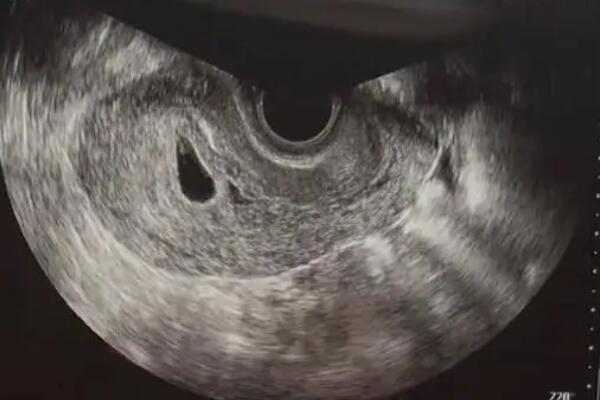

试管婴儿(in vitro fertilization,试管婴儿)即在体外受精及胚胎培育。它通过将母亲的卵子和父亲的精子置在体外完成受精,进而让健康的胚胎获取发育的机会,并再次植入自己身体内,令母亲怀孕。在试管婴儿过程中,B超的检测是1个必不可少的步骤,通过B超能够对自己体内的卵巢,卵泡的大小,分布,外观和数量以及黄体部分行动等进行评估,察看病人是不是具有受孕的条件和准备受孕卵的筹备情况,进而审定

在孕早期出现先兆流产征兆时,B超检查是评估胚胎存活状态的关键手段。通过经阴道或腹部超声波,医生可清晰观测孕囊位置、卵黄囊发育及原始心管搏动情况。对于有复发性流产史或辅助生殖受孕的孕妇,临床指南建议通过系列B超动态监测胚胎发育速度,这与单次检查相比能更早发现胚胎停育风险。现代超声技术采用声波成像原理,其辐射量仅为环境背景值的千分之一。2021年中华医学会围产医学分会发布的《早孕期超声检查规范》明确指